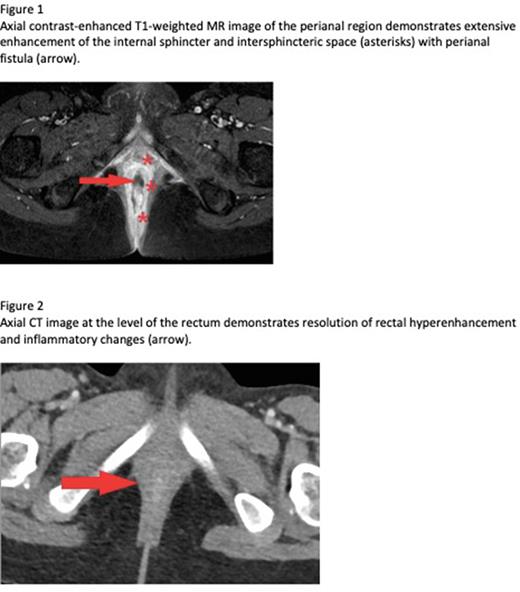

Case: A 7yoF presented with fever and pancytopenia in the setting of Human Metapneumovirus and Parainfluenza. Bone marrow biopsy showed hypocellularity (60-70%) with granulocytic and megakaryocytic hypoplasia, favoring viral suppression. Ultimately, she progressed to transfusion dependence. Repeat bone marrow aspirate and biopsy ultimately revealed bone marrow aplasia, DEB chromosomes, telomere lengths, and PNH clones were negative, confirming the diagnosis of vsAA. She was subsequently admitted for febrile neutropenia (F&N) and was found to have mild respiratory COVID-19, but began to complain of rectal pain that was initially attributed to her history of constipation. She defervesced on IV antibiotics (abx) and was discharged home with negative cultures. Within a week she represented with hematochezia and F&N and was found to have proctitis with perianal fistula on MRI (figure 1); GI PCR panel was + Enteroaggregative E. coli, no resistant organisms were identified. She clinically improved and discharged on IV piperacillin-tazobactam (pip-tazo). Despite 2 weeks of IV abx, she developed new fever and imaging confirmed persistent proctitis with peri-rectal abscess. As she had limited response to abx alone we trialed a short course of granulocytes with improvement in anorectal inflammation by CT. She was discharged with a plan to continue IV pip-tazo until achieving radiographic cure; however, interval imaging after an additional 2 weeks of abx showed rebound of her proctitis and she was again admitted with F&N and rising inflammatory markers. Her failure to eradicate her peri-rectal infection despite prolonged antibiotics (>4weeks), along with her previous response to a short course of granulocyte transfusion prompted us to prescribe a prolonged 10-day course of granulocytes with continued antibiosis. Her post-granulocyte CT showed resolution of her perirectal abscess and proctitis (figure 2). With resolution of her infection, she was able to proceed to HSCT which she completed without recurrence of her anorectal infection.